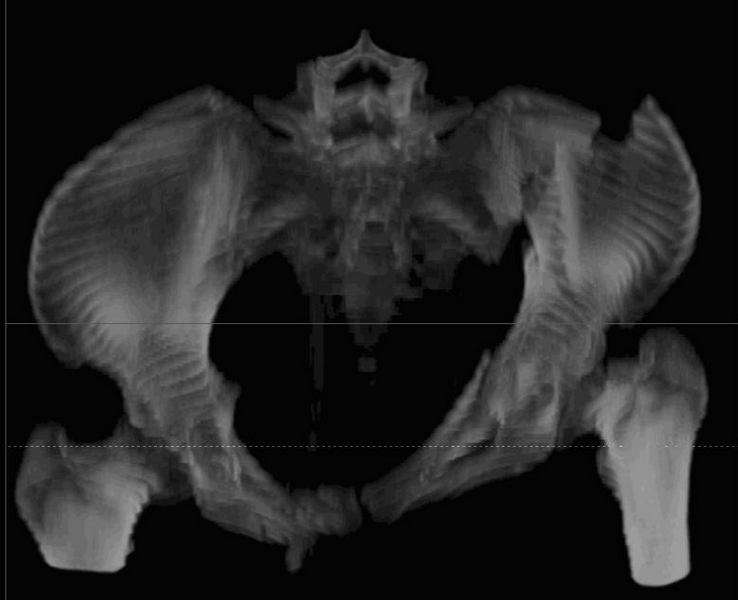

Уважаемые коллеги! С прошедшеми Вас праздниками. Теперь ближе к трудовым будням. Поступила 16 летняя девушка неделю назад. Механизм травмы падение с 5 этажа. Краткий диагноз:закрытый перелом левой ключицы, левого плеча, закрытый вертикально и ротационно нестабильный перелом костей таза:закрытый перелом левой подвздошной кости, переломы лонной кости справа, перелом обоих колонн вертлужной впадины слева;субкапитальный перелом шейки левой бедренной кости со смещением. По тактике лечения таза возникли следующие вопросы: 1. С чего начать - фиксации переломов вертлужной впадины или устранения деформаций таза? 2. Надо ли фиксировать шейку или фиксировать бедро в аппарате вместе с тазом, а после сращения таза планировать ТЭП ТБС? Если имеются еще какие подводные камни, будем рады выслушать.Спасибо.

На снимке ацетабулума редко встречающийся очень низкий перелом, наверное, трудно было репозицию через один доступ? Перелом как бы замкнулся в квадрилатеральной поврехности.

Ничего такого особенного в переломе вертлужной впадины не опознал. Транстектальный перелом хорошо репонируется щипцами, установленными через седалищную вырезку.

В положении на спине подвздошным и надлобковым доступом восстанавливается тазовое кольцо, фиксация пластинами. При хорошей репозиции может улучшиться конгруэнтность в суставе.

Затем, если положение хорошее, закрытый остеосинтез шейки винтами.

Если нет - в положении на боку, синтез задней колонны из наружно-латерального доступа и синтез головки винтами, но уже под визуальным контролем.

На картинке подобный случай, только без шейки, сделано через месяц или полтора после травмы.